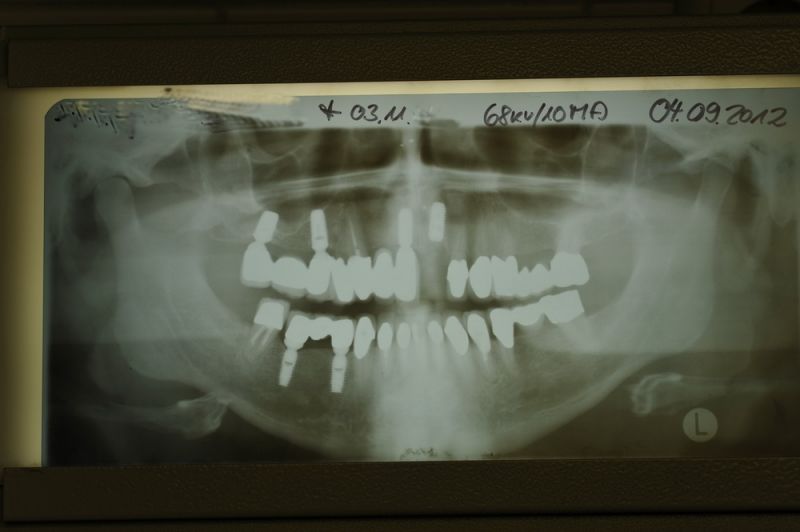

Kieler Patient erhält implantatgetragene Frontzahnbrücke

Dieser Patient fällt ein bißchen aus dem üblichen Rahmen, weil die vielfachen Versorgungen hier nicht zeigtlich im Rahmen einer CMD Behandlung erbracht wurden, sondern über viele Jahre hinweg nach und nach.

Der Patient wurde von dem Praxisvorgänger übernommen und befindet sich daher seit weit über 20 Jahren hier in Behandlung.

Dieser Patient hat keine funktionellen Beschwerden und aufgrund der geschilderten Vorgehensweise war es niemals Ziel der Behandlung die bestehenden Bissverhältnisse zu untersuchen, oder therapeutisch zu verändern, weil der Patient zu den Patienten gehört, die mit einem fehlerhaften Biss, wir nennen es Habituelle Okklusion, keinerlei Probleme und Beschwerden hat.

Was man an diesem Fall gut zu erkennen vermag, dass Patienten, die für sich irgendwann entschieden haben, nicht mit einem herausnehmbaren Zahnersatz ihren Lebensabend verbringen wollen auch nach und nach auf eine Implantatpfeilerstützzahl kommen, die genügend Substanz für die Lebensphase bieten, in der körpereigene Stützsubstanz, in Form von Zähnen zunehmend verloren geht.